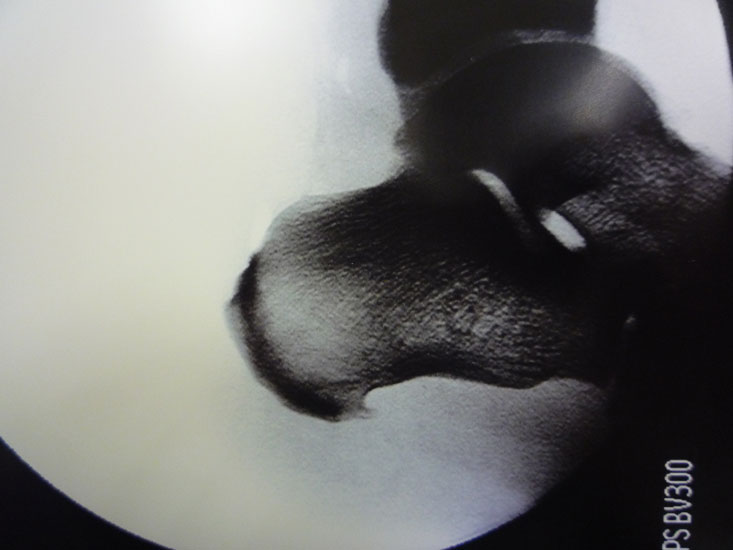

Abbildung 10, Video 5

Das OP-Ergebnis wird mit dem Bildwandler dokumentiert. Hierbei ist es wichtig, auch mediale und laterale Schrägaufnahmen anzufertigen, um keine weit posteromedial oder -lateral gelegenen Exostosenreste zu übersehen (Calcaneus seitlich, sowie 45° Innen- und Außenrotation). Ergänzend zu Röntgenaufnahme sollte der mediale und laterale Calcaneus abgetastet werden, um das Risiko einer belassenen Knochenkante möglichst gering zu halten. Der Hautverschluss erfolgt in Einzelknopftechnik, eine Ruhigstellung ist nicht erforderlich.